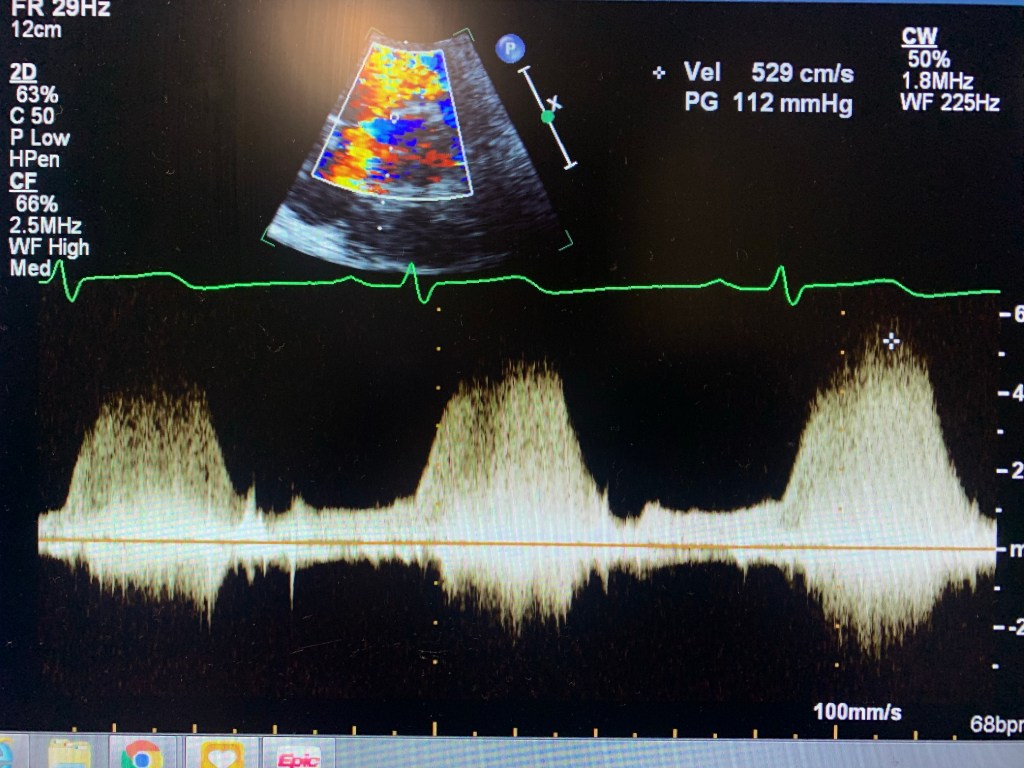

Echocardiogram of a VSD

Case study: a 32 y/o female, w/ shortness of breath, known VSD.

I knew about the problem since the patient told me about it and it was mentioned in the chart. I started with Parasternal Long axis and looked for a flow by using Doppler. Once I found it, I used PW and CW to get the velocity. Then moved to Parasternal Short. Since the VSD was at 11 o’clock, it was an indication that it was a perimembranous VSD. Use color Doppler, lower the scale, take pictures and PW and CW too. Same in Apical 4, 5 and 3. Later I went to ask the MD if they needed contrast. Which I used later. Don’t have pictures here because the color Flow didn’t look good. But I had similar velocity. And always try a higher window at the parasternal. Instead of PEN, use GEN. The color Doppler will look better.